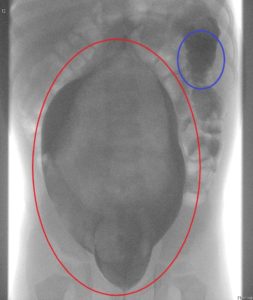

Es wurde ein Kontrastmittelröntgen gemacht. Bei diesem Röntgen hörte man vom Arzt und den Assistentinnen immer mal ein „Ohhh, da geht aber einiges an Kontrastmittel rein…“ Da das Ergebnis echt krass war, wurde auch direkt ein Biopsie Termin vereinbart.

Rot eingekreist ist der geweitete Dickdarm (Megakolon) zu erkennen. Er war zu diesem Zeitpunkt etwa um das Fünffache geweitet. Blau eingekreist ein normal weites Stück Dickdarm.